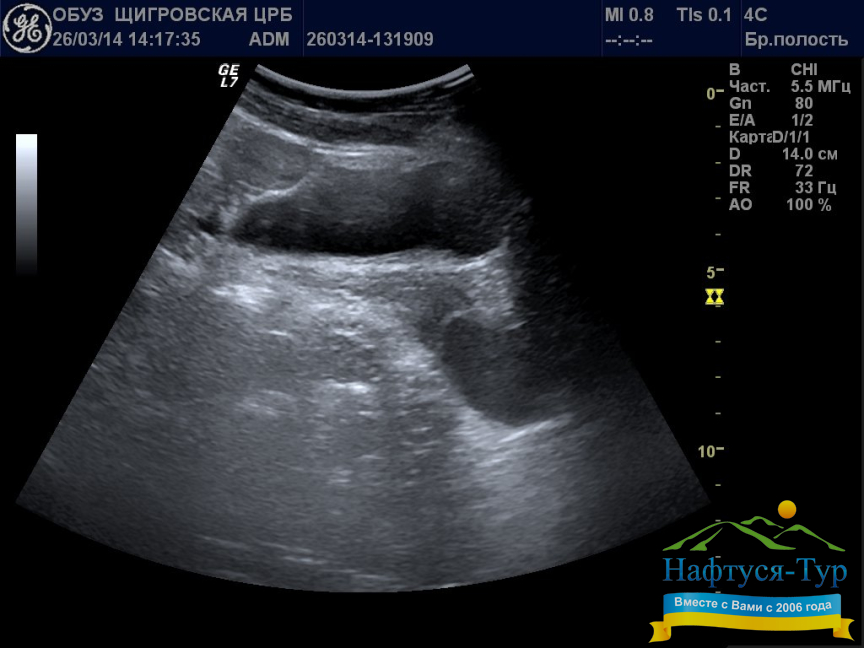

УЗИ (Ультразвуковое исследование) на сегодняшний день выступает одним из главных средств при диагностике чрезвычайно широкого спектра заболеваний. Соответственно, кабинет УЗИ имеется в любом санатории Украины, различия между здравницами в этом смысле могут состоять лишь в уровне используемой аппаратуры. Например, ряд современных аппаратов позволяют создавать 3D или 4D изображения внутренних органов, что резко повышает качество диагностики. К безусловным преимуществам УЗИ относятся неинвазивность, скорость, полная наглядность получаемых результатов и многие другие. Эти преимущества, в свою очередь, позволяют многократно и с высокой эффективностью использовать УЗИ на этапе первичной диагностики, а также в ходе проведения курса лечения для определения результатов, достигаемых на каждом этапе.